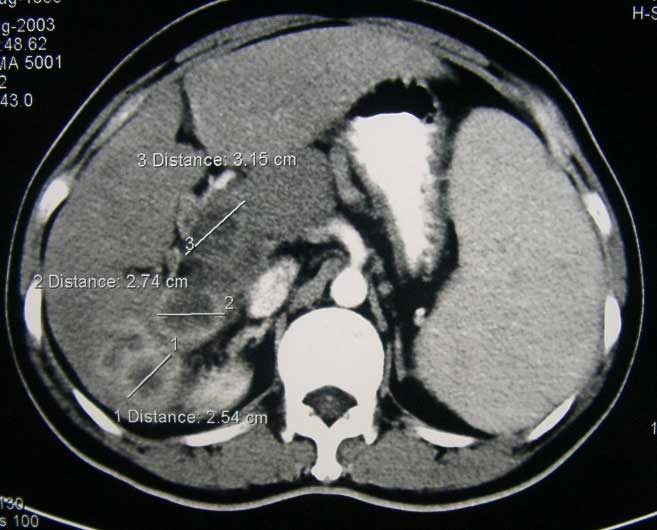

Pang dirujuk ke spesialis bedah di rumah sakit swasta. Hasil CT-scan menunjukan hepatoma lobus kanan dengan ukuran 8 x 7 x 8 cm pada segmen 6 dan 7. Pang menjalani operasi reseksi tumor pada 25 Maret 2008. Operasi ini menghabiskan biaya 20.000 RM.

Pang menjalani terapi ini dari September 2008 sampai Februari 2009 dan melakukan total 5 sesi. Tapi hasilnya mengecewakan. Hasil CT-Scan menunjukkan metastasis ke paru-paru. Jumlahnya ada 5 nodul pada paru-paru kiri dan kanan. Ukurannya berdiameter sekitar 6 sampai 12 mm masing-masing. Hasil CT-Scan juga menunjukkan 2 partially nekrotik tumor pada Segmen 7/8 dari livernya. Ukurannya berdiameter kira-kira 4,5 x 6 cm dan 3,5 x 3,5 cm masing-masing.